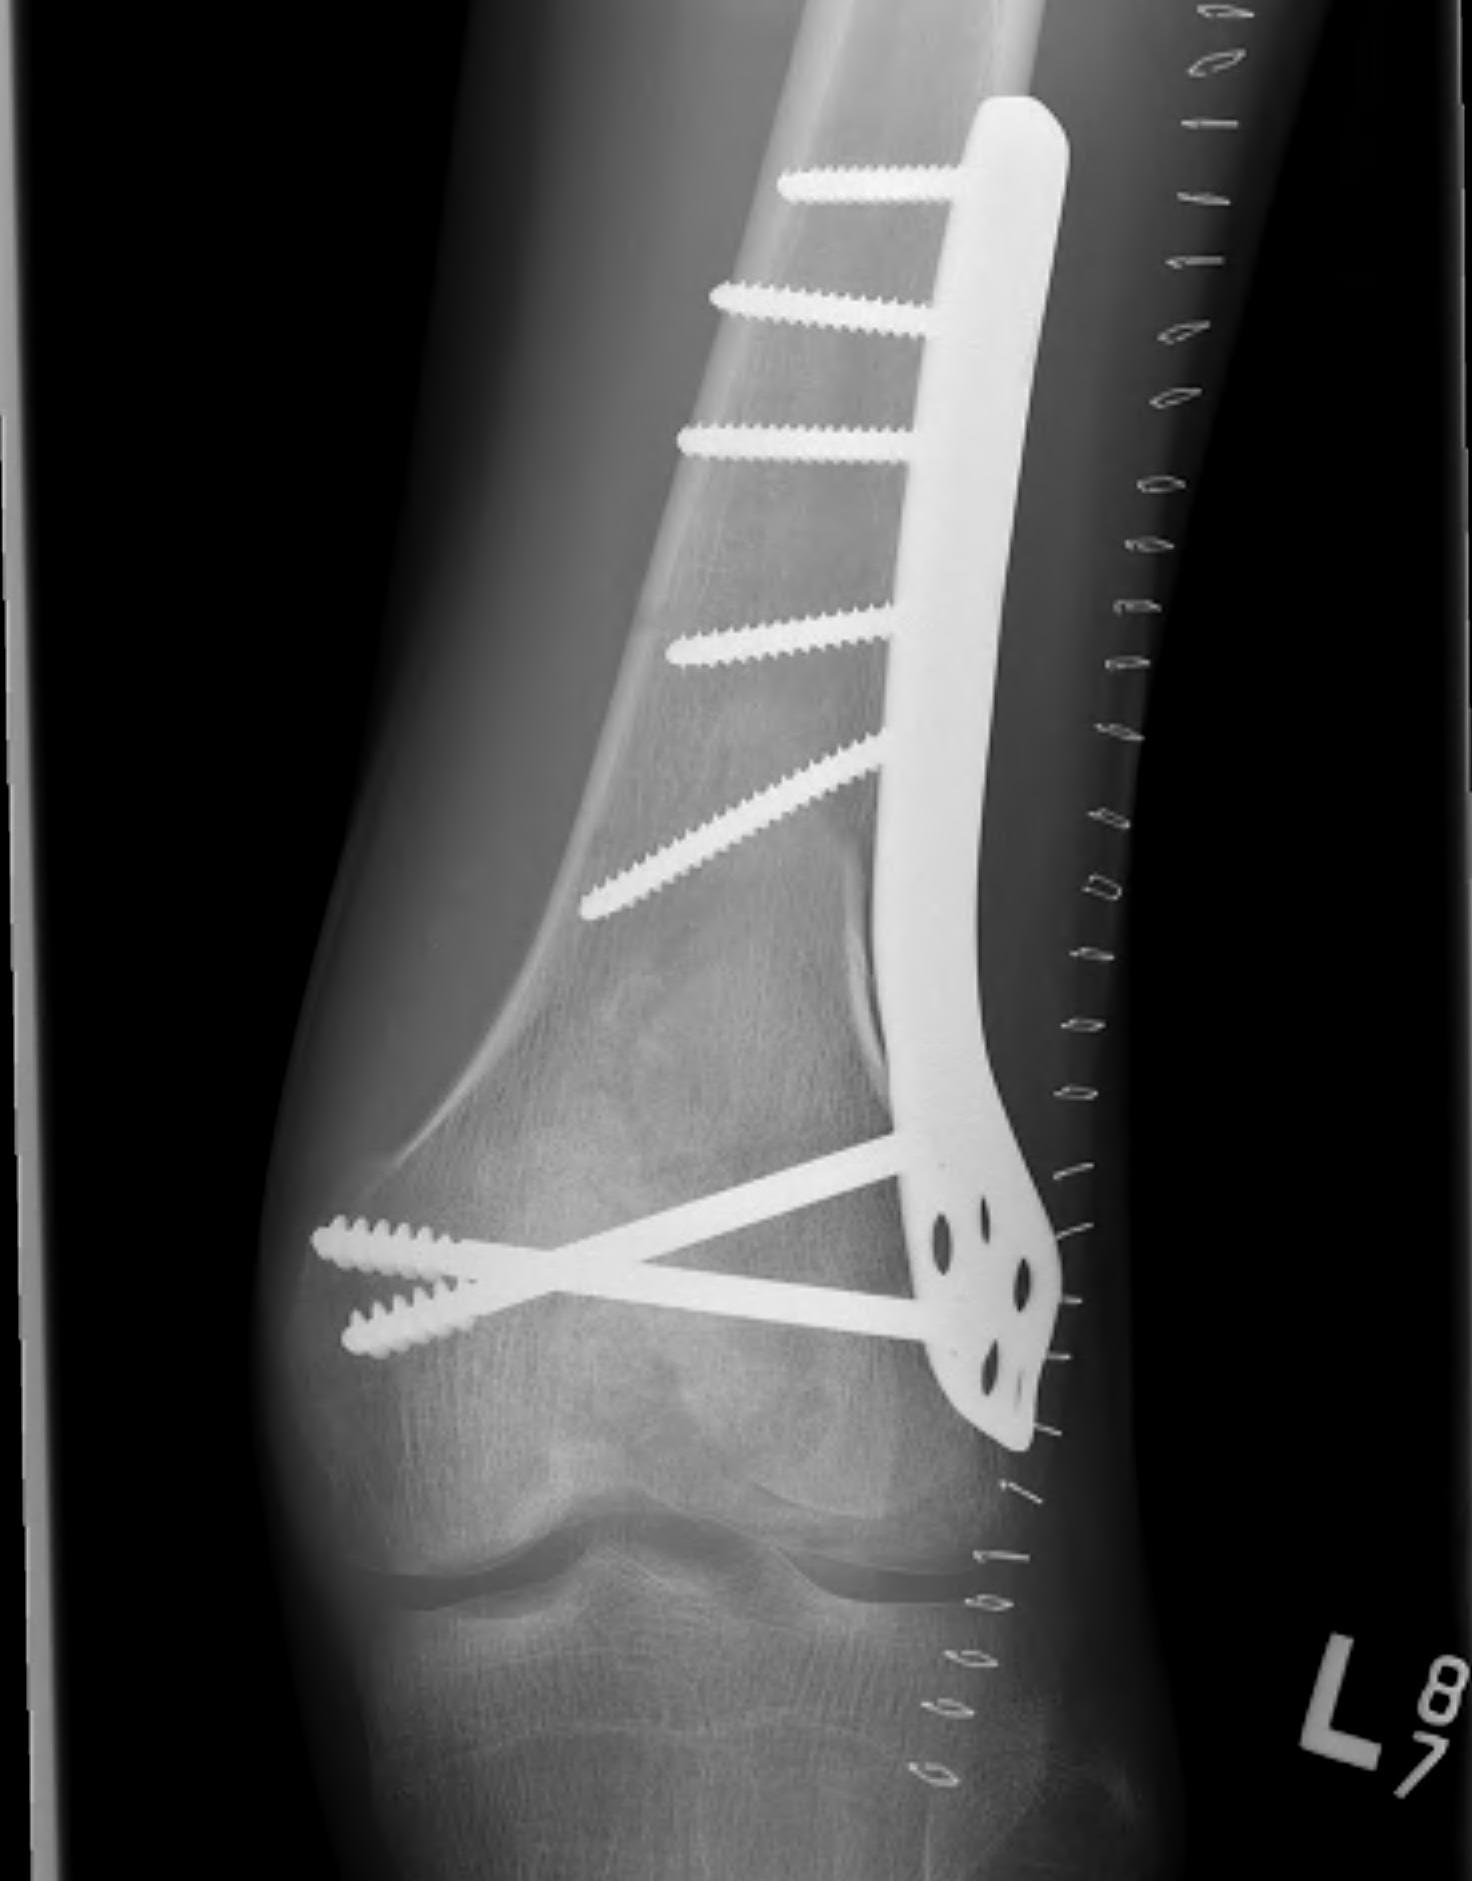

Weight bearing joints

Options

Currettage and bone graft

Currettage / bone graft / fixation